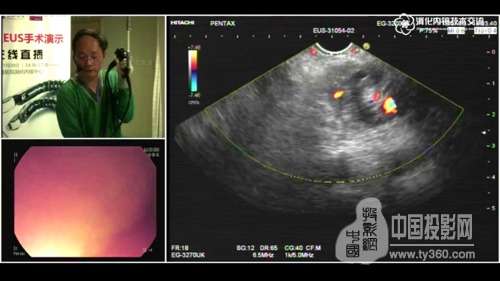

圖3:手術畫面實時傳送到技術研討會現場

華平股份智慧醫療產品總監,長海醫院數字化手術室項目負責人易曉表示:“在語音和圖像輸出方面,我們采用了華平獨有的光纖影像傳輸技術,實現廣播級影像傳送,1080P的圖像質量,可達到會診級別,完全滿足醫學專家學術研討對圖像質量的要求。”